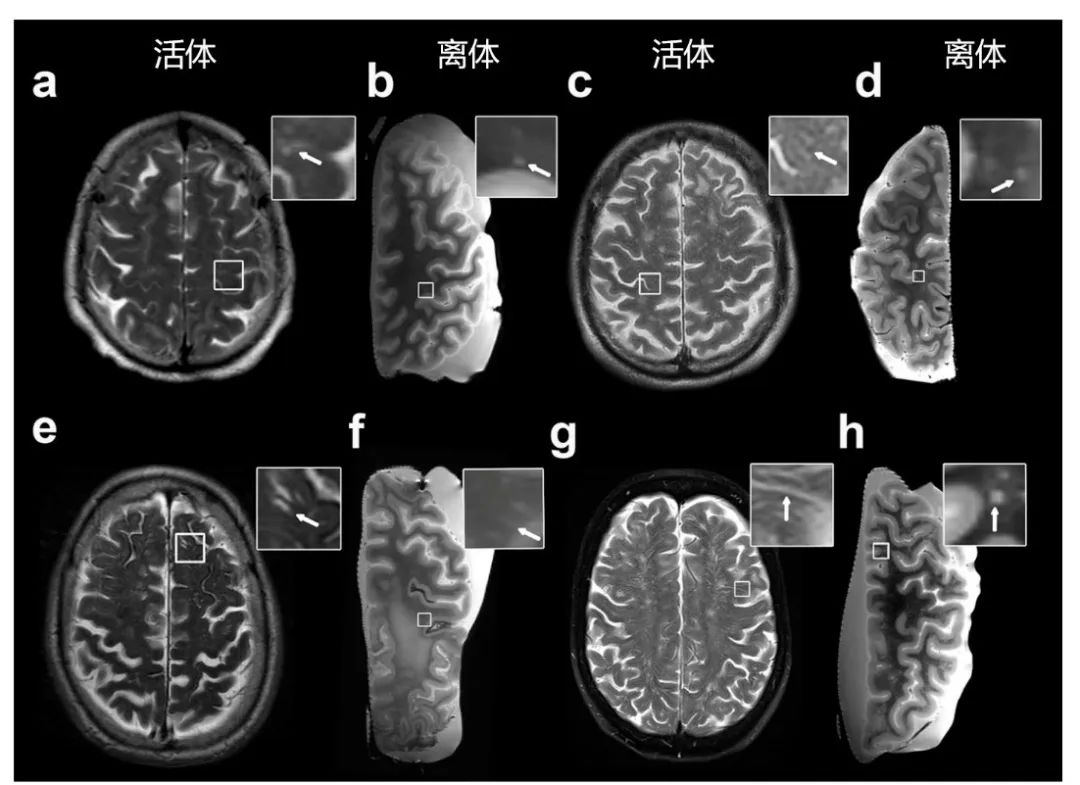

MRI可见PVS的体内负荷与体外MRI负荷相关。活体MRI评估的MRI可见PVS程度,分别与离体MRI评估的严重程度呈正相关(CSO: Spearman's ρ=0.58,P<0.001;BG:Spearman ρ=0.20,P=0.039)。总的来说,该研究证实了既往研究,与非CAA对照组相比,CAA病例中CSO中MRI可见PVS的程度更高,但基底节区(basal ganglia, BG)中没有(图8)。此外,更为重要的是,在福尔马林固定一段时间后,离体MRI似乎始终能捕捉到PVS的程度。

图8. 活体(a, c, e, g)和离体(b, d, f, h) MRI-T2可见PVS

此外,MRI可见的PVS的严重程度在基底节和四个近侧白质区域的离体MRI上进行了额叶、颞叶、顶叶和枕叶等区域性评估(图9)。在体外MRI上,局部MRI可见的PVS严重程度与组织病理学上的EPVS面积相关。在组织病理学上,MRI可见的PVS对应于白质血管周围的间隙扩大。值得注意的是,大多数间隙似乎不是完全空的,而是包含细胞以及网状外观的细胞外基质,偶尔有含铁血黄素沉积物。离体组织3T-MRI扫描可见PVS区域评分与组织病理学上的EPVS面积百分比呈正相关(Spearman's ρ=0.408,P<0.001),上述结果表明离体MRI上的PVS可准确地反映组织病理学上的PVS扩大。此外,与非CAA患者相比,CAA患者存在组织病理学上更为严重的EPVS(P<0.001)。